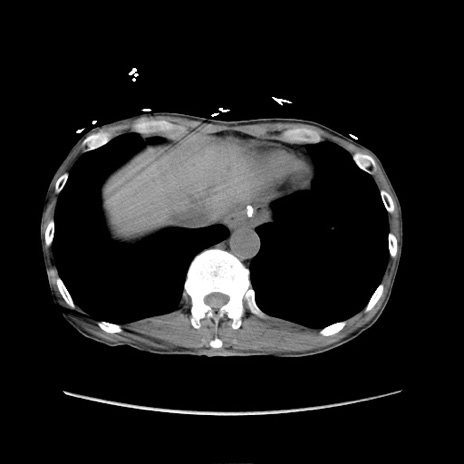

症例11(横断像)

【症例】 60歳代男性

【主訴】 下腹部痛

【現病歴】 本日夜中より下腹部痛の症状認め、受診。

【既往歴】 膀胱癌(膀胱全摘+尿管皮膚瘻術) 、胃癌術後

【身体所見】 BT 35.3℃、PR 58/min、BP 136/98mHg、腹部平坦、軟、腸蠕動音±、ストマ留置あり、左上腹部~正中部に圧痛あり、反跳痛なし。

【データ】WBC 5100、CRP0.01